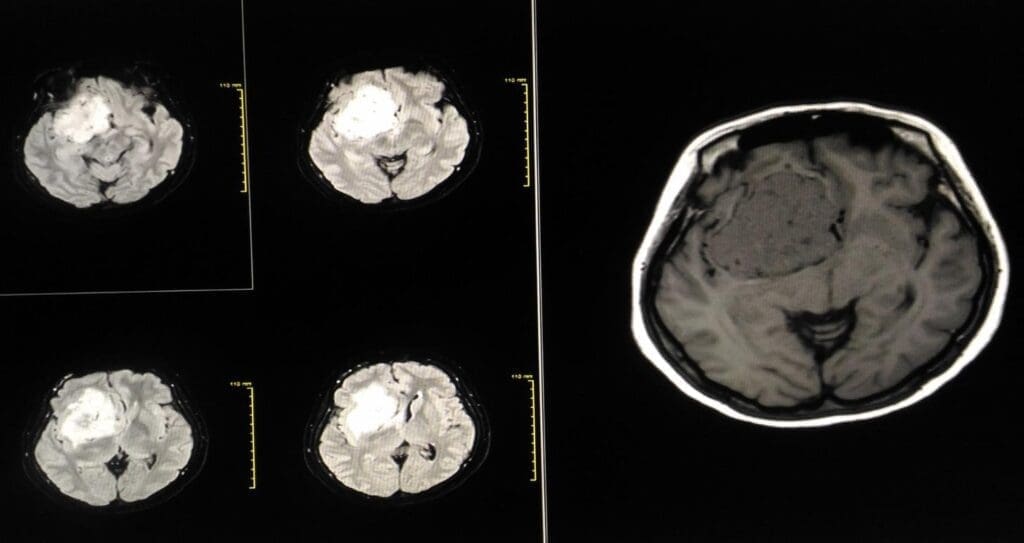

Advanced Imaging for Surgical Mapping

Advanced imaging is key for surgical mapping. It lets us see the tumor and brain structures clearly. MRI and CT scans help us understand the tumor’s size and where it is in the brain.

A leading neurosurgeon says, “Advanced imaging is not just for diagnosis; it’s a guide for surgery.” This shows how vital accurate imaging is for planning the surgery.

“The use of advanced imaging techniques has changed neurosurgery, making surgeries more precise and safer.”

Functional MRI and Tractography

Functional MRI (fMRI) and tractography map brain functions and paths. They show where tumors are in relation to important brain parts. This helps in more precise surgical planning.